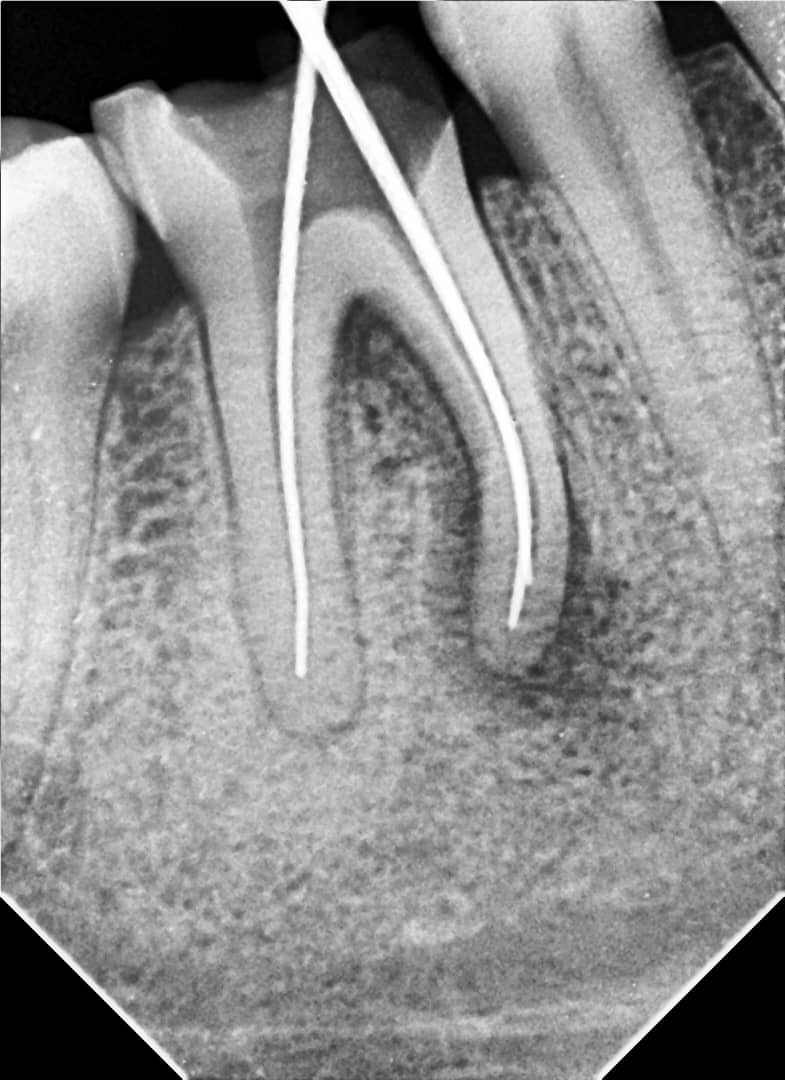

Treatment:

- Mechanical instrumentation using SUPER FILES III rotary files up to size F3

- Irrigation with 3.25% sodium hypochlorite (NaOCl)

- Intracanal calcium hydroxide dressing for 2 weeks with a temporary filling